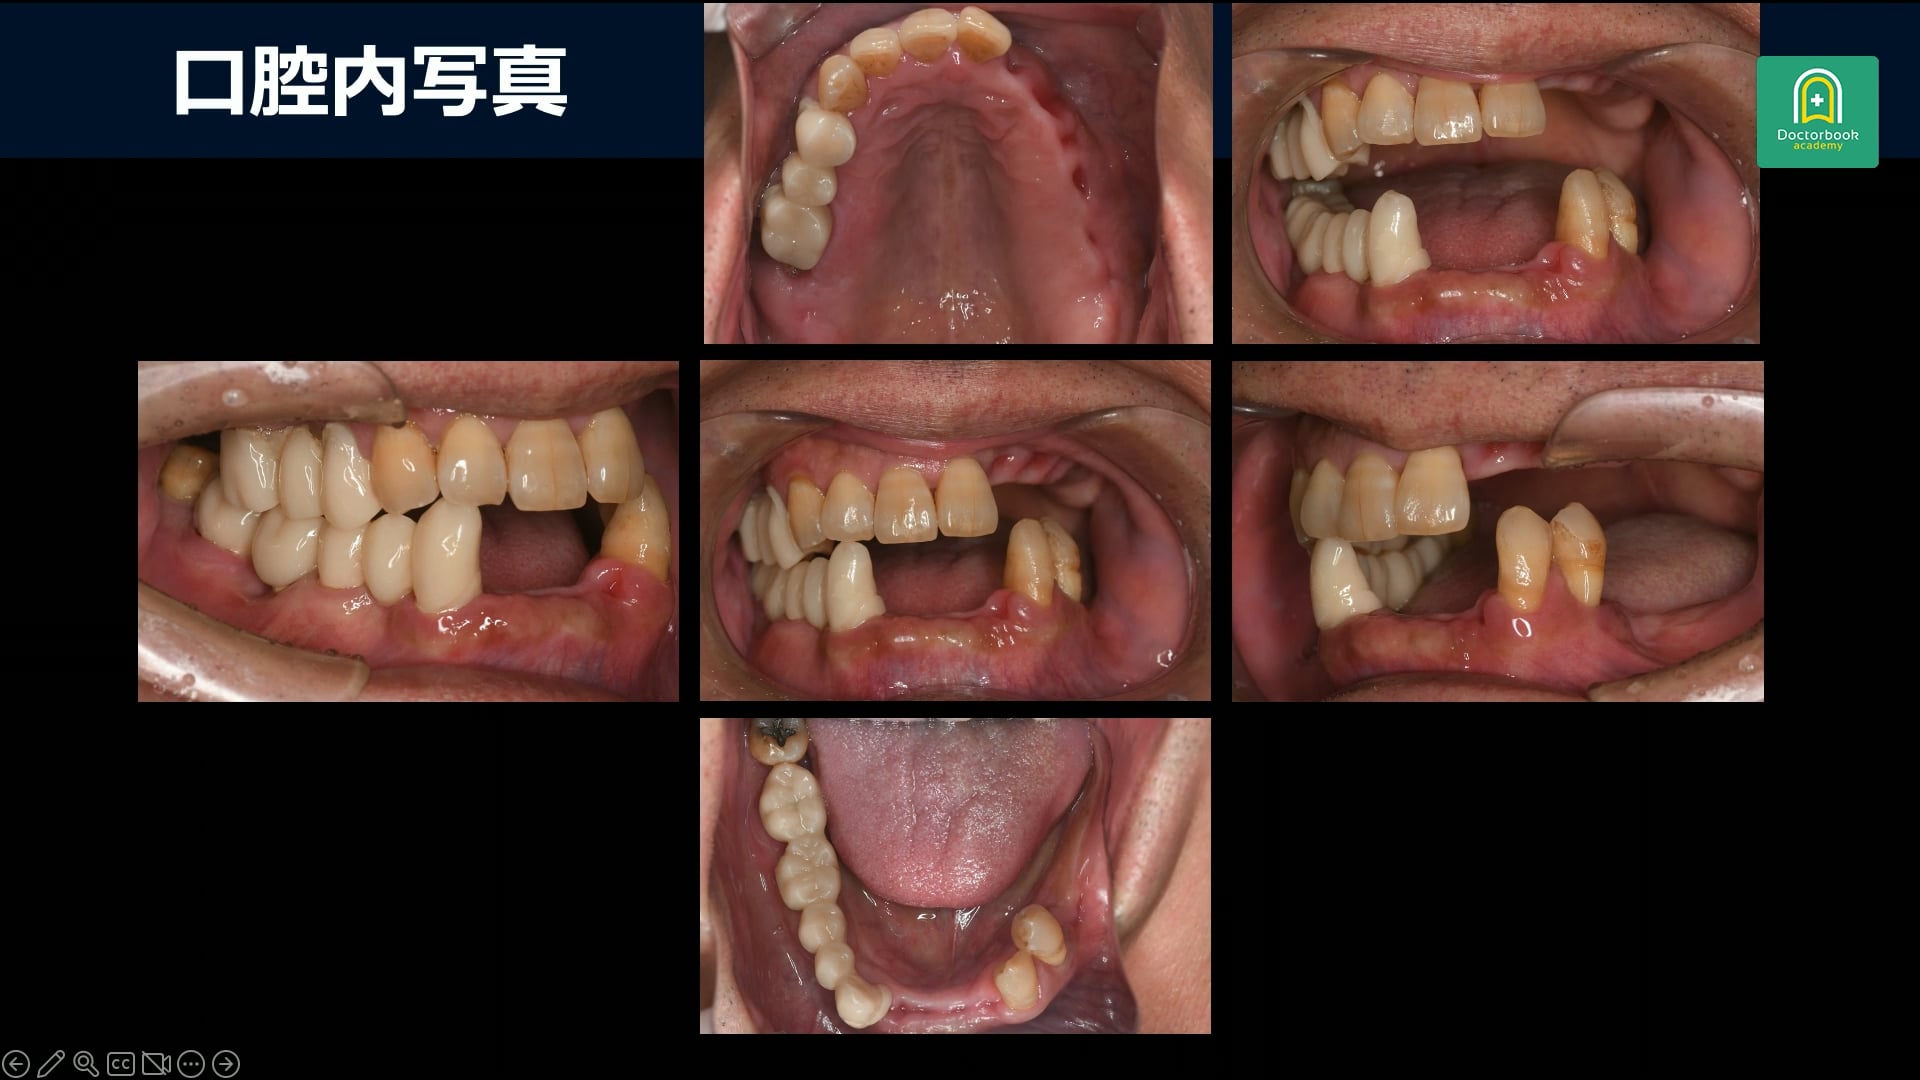

まずは口腔内写真です。

右側は臼歯部で早期接触がありそれが原因で噛めないと考えます。

過去に入れ歯を入れていたがほとんど使っていないようです。